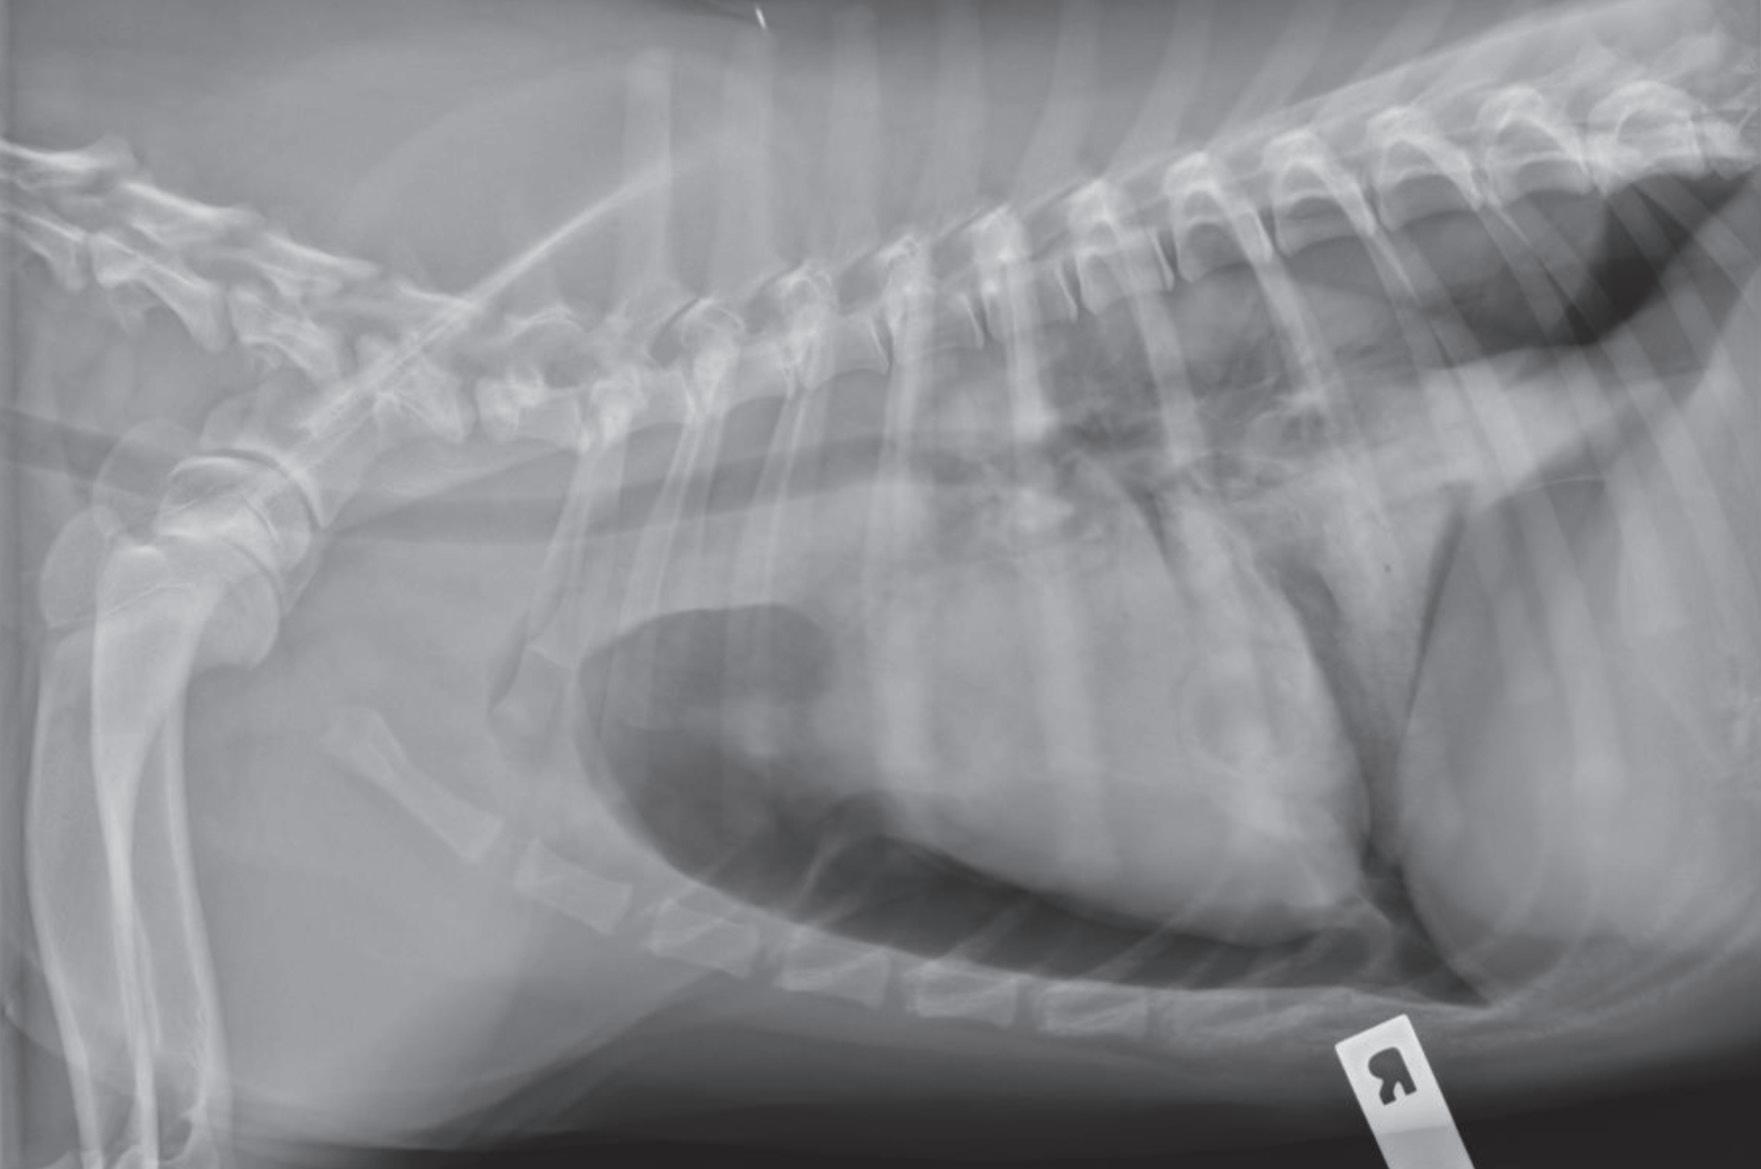

Respiratory emergencies: a review

c. BREATHING: A distant, visual assessment of the breathing effort and pattern will assist in localizing the respiratory problem (Table 1).